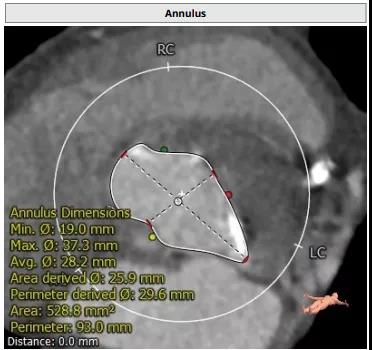

患者男性,67岁,头晕伴胸闷、胸痛6月余,术前心脏超声提示主动脉瓣增厚钙化伴重度狭窄,峰值流速4.9m/s,峰值压差94mmHg,平均跨瓣压差59mmHg,瓣口面积0.6cm2。CT显示主动脉瓣为Type I型二叶瓣,瓣叶边缘及左右冠瓣融合嵴严重钙化,致瓣口极度细窄。瓣环面积528.8mm2,测算直径25.9mm,左冠脉开口高度14.4mm,右冠脉开口高度17.5mm。患者合并重度肺气肿、多发肺大泡、支气管扩张,肺功能极差,静息状态下氧饱和度仅约80%,STS评分8.6%,属于外科手术高风险患者。

主动脉瓣瓣环 Type I型二叶瓣